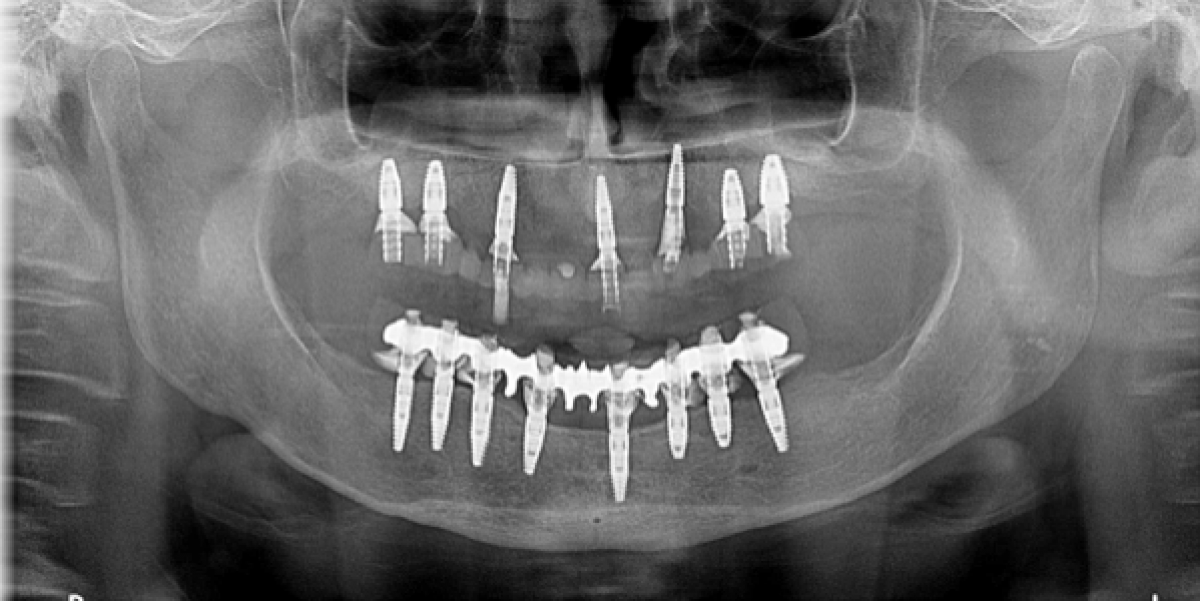

X-ray examination with orthopantomography showed severe periodontal disease in the few remaining teeth in the arches and significant bone resorption in the maxilla, resulting in a severe loss of vertical dimension. Cone Beam CT is required in order to establish a proper treatment plan. (PICTURE 1,2)

The second surgical phase involves, therefore, the remaining teeth extraction in the upper and lower arch, the positioning of the implant surgical guide and the insertion of 7 implants and 4 mini implants in the upper arch and 8 implants in the lower arch.

In both arches an immediate load is realized; in the upper arch in particular, however, this is possible by using the mini implants, as the quality of the bone did not allow for primary stability and sufficient torque (35N) to load the implants. Therefore, we will wait 4-6 months and then perform a traditional loading. (PICTURE 4)